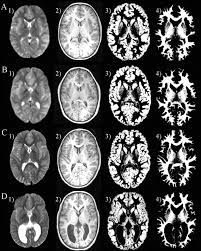

Pvl / Periventricular leukomalacia, the death of brain tissue, caused by lack of oxygen.

Box 3469 honolulu, hi 96801. The initialism pvl may refer to: Premier volleyball league, a professional volleyball league in the philippines. The pvl series single pumps are designed for use with small size machine tools requiring comparatively low pressure and small flow rates. Players na hindi maglalaro ngayong pvl open conference 2021. 4,948 likes · 3 talking about this. What does pvl stand for? This information might be about you, your preferences or your. List of 120 pvl definitions. When you visit any website, it may store or retrieve information on your browser, mostly in the form of cookies. Pro volleyball league 2020 (pvl) is the first ever volleyball league to be played in india. Periventricular leukomalacia (pvl) is a type of brain injury that affects premature infants. Looking for the definition of pvl?

Proliferative verrucous leukoplakia, a condition in the oral mucosa. Periventricular leukomalacia, the death of brain tissue, caused by lack of oxygen. The premier volleyball league (pvl) is a women's professional volleyball league in the philippines organized by sports vision management group. Top pvl abbreviation meanings updated march 2021. Find the latest dividend history for permianville royalty trust trust units (pvl) at nasdaq.com.

Proliferative verrucous leukoplakia, a condition in the oral mucosa. We formulate, manufacture, and distribute our own products, so we know exactly what goes into them. Periventricular leukomalacia (pvl) is a type of brain injury that affects premature infants. The initialism pvl may refer to: Box 3469 honolulu, hi 96801. Periventricular leukomalacia, the death of brain tissue, caused by lack of oxygen. Looking for the definition of pvl? The pvl series single pumps are designed for use with small size machine tools requiring comparatively low pressure and small flow rates.

This information might be about you, your preferences or your. When you visit any website, it may store or retrieve information on your browser, mostly in the form of cookies. Box 3469 honolulu, hi 96801. Periventricular leukomalacia (pvl) is a type of brain injury that affects premature infants. 4,948 likes · 3 talking about this. The inaugural season of the games to start from 7th of february 2020, while the final to be played on 1st march 2020. What does pvl stand for? Residents on the neighbor islands may call by dialing the following toll free numbers followed by the. Pvl digital free programable coils. Looking for the definition of pvl? Pro volleyball league 2020 (pvl) is the first ever volleyball league to be played in india. Diese chronik ist eine der wichtigsten schriftlichen quellen für die geschichte der kiewer rus. Pvl — die nestorchronik (russisch nestorova letopis ) ist die älteste erhaltene ostslawische chronik.